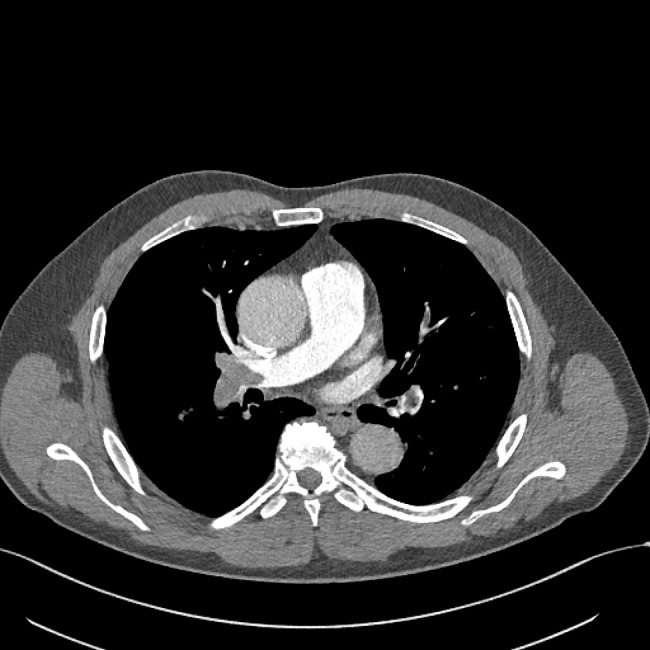

Case presentation: In this case series, we demonstrate a typical ESN pattern on RVOT Doppler evaluation in three patients with intermediate-risk PE presenting to our emergency department (ED). None of the patients had been previously diagnosed with pulmonary hypertension or other chronic pulmonary and cardiac disease. The pre-test probability was low. Massive proximal emboli were found on CT angiograms, involving pulmonary truncus or main pulmonary arteries. Previously, the ESN pattern was identified on a focused echocardiogram, which was the only echocardiographic indicator of increased pulmonary vascular resistance.